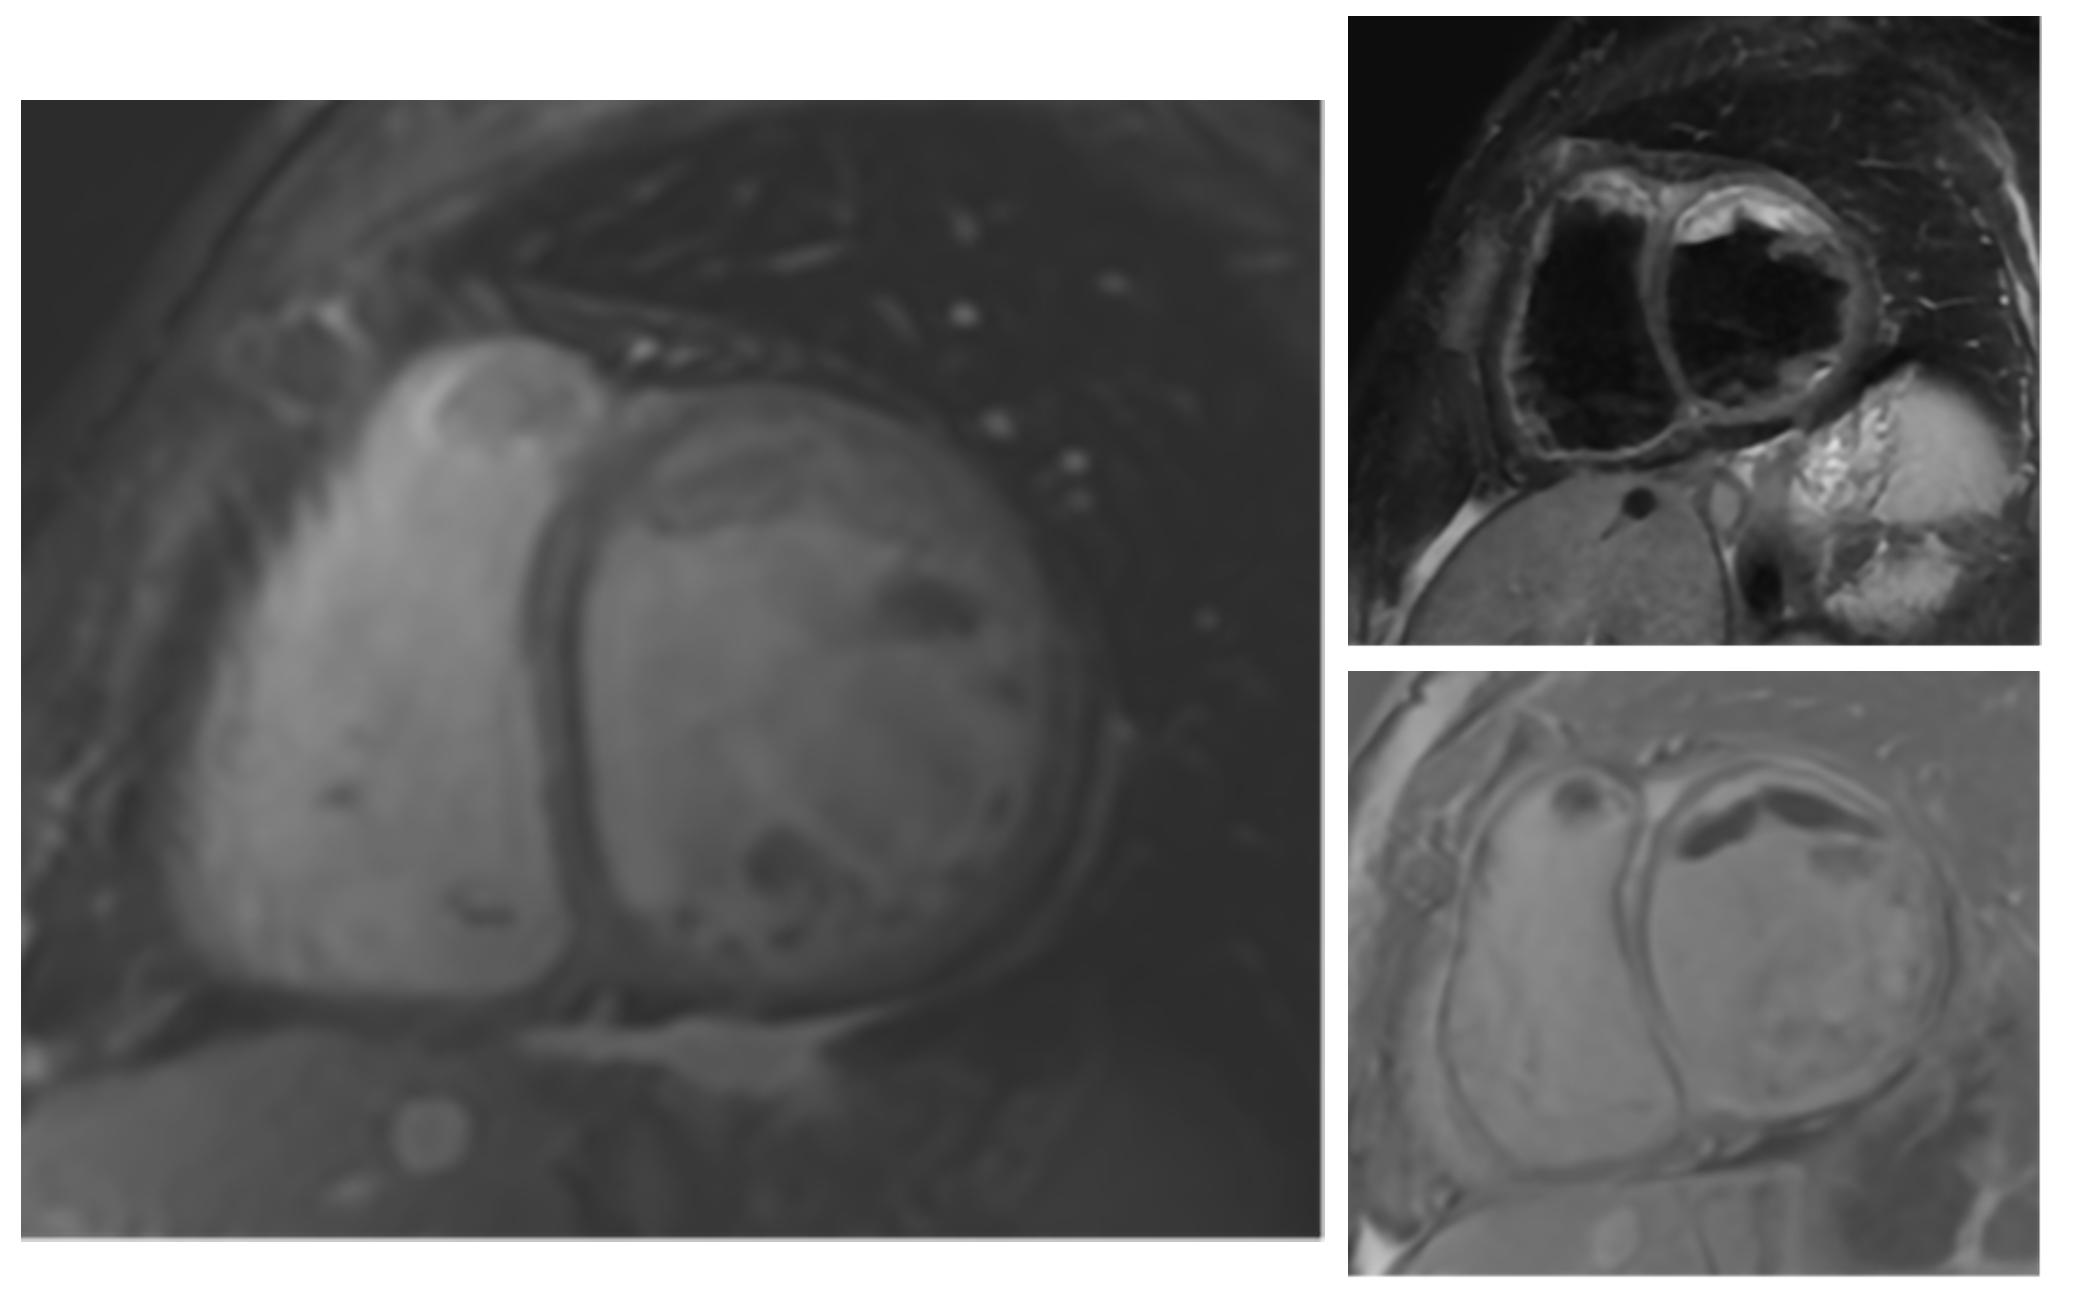

Second CMR: 4 Chamber view with LGE and 3 Chamber view showing both LV and RV thrombi